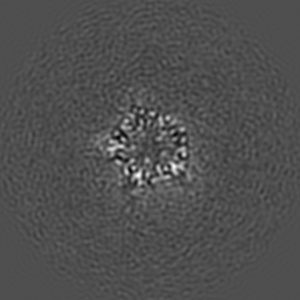

Cyro-EM structure of human Glycine Receptor alpha2-beta heteromer, glycine bound, (semi)open state

Sample: Glycine receptor alpha2-beta heteromer, glycine bound, open state

Characterization of the subunit composition and structure of adult human glycine receptors

Yu H, Bai X-C, Wang W

(2021) Neuron , 109 , 2707 - 2716